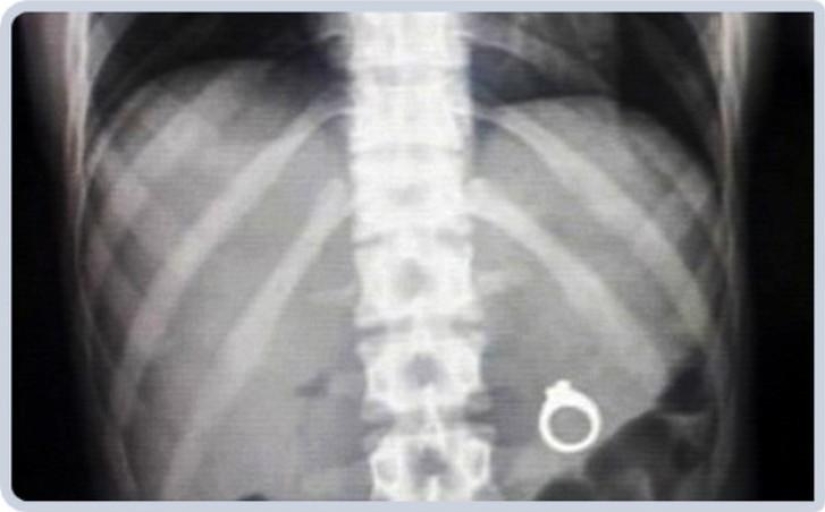

3. Wedding ring.